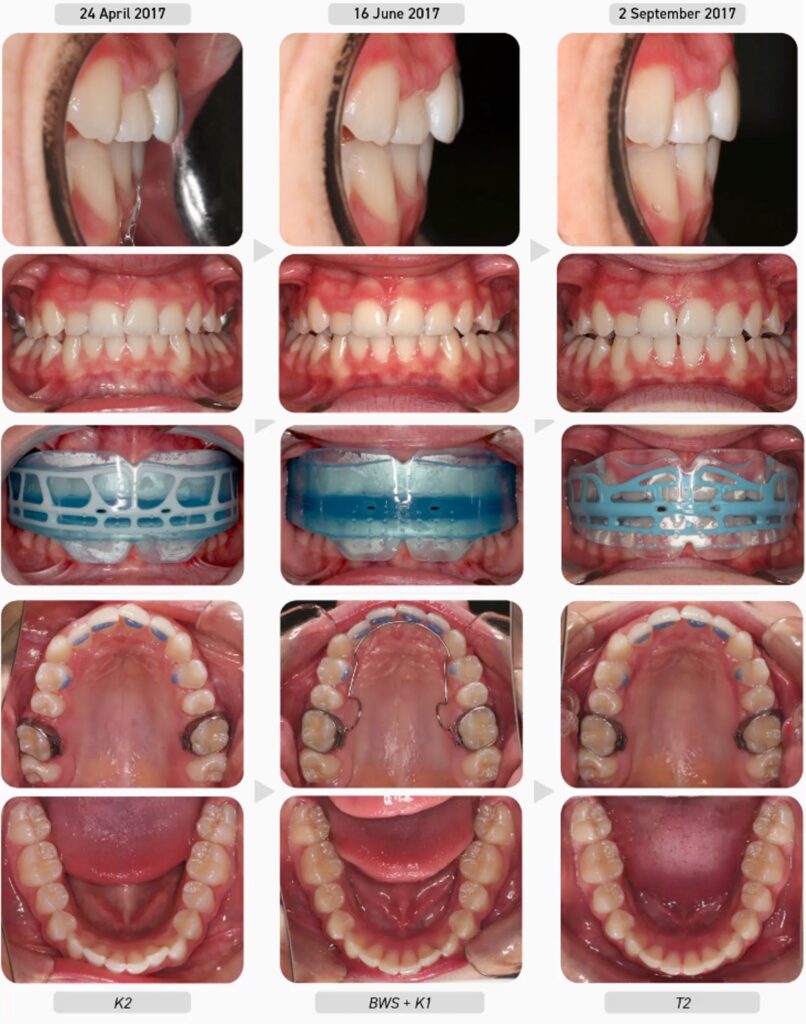

Tiến trình điều trị:

Bệnh nhân bắt đầu với khí cụ K1 để thiết lập thở bằng mũi và bắt đầu điều chỉnh các thói quen cơ chức năng. Ba tháng sau, chức năng hô hấp của bệnh nhân đã được cải thiện và do liên tục duy trì được K1 qua đêm nên được chuyển sang đeo khí cụ K2 (lớn) tập trung vào phát triển cung răng và tiếp tục điều chỉnh thói quen.

Có thể thấy sự cải thiện hình dáng cung răng và sự thẳng hàng của các răng trước trên dưới chỉ sau 3 tháng điều trị. Bệnh nhân ở hệ răng vĩnh viễn thường xuyên yêu cầu mở rộng cung răng trên để không chỉ tạo khoảng cho răng mà quan trọng hơn là di chuyển các răng ra khỏi vị trí để tạo điều kiện cho lưỡi có tư thế đúng trong vòm miệng. Vì vậy, quyết định sử dụng BWS. BWS phải được kết hợp với khí cụ giai đoạn 1 nên K1 (lớn) đã được cấp lại cho bệnh nhân đeo.

Lưu ý rằng sau hai tháng rưỡi nới rộng với BWS, các R6 hàm trên bắt đầu di xa. Khi điều này xảy ra, dây cung sẽ được tháo ra để răng cối lớn ổn định trở lại và bệnh nhân được cho đeo lại khí cụ K2. Hai tháng sau, bệnh nhân đã sẵn sàng bước vào đợt nới rộng BWS thứ hai để phát triển hàm trên hơn nữa và cải thiện chức năng nên K1 đã được cấp lại. Ba tháng sau, quá trình nới rộng BWS hoàn tất và bệnh nhân được cấp khí cụ T2.

Lưu ý overjet tăng nhẹ sau mỗi lần nới rộng với BWS. Điều này là thuận lợi vì nó cho phép hàm dưới lùi dần về phía trước khi cung hàm trên phát triển.